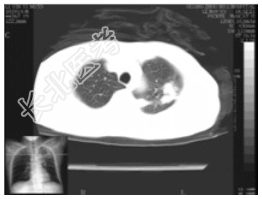

- [材料题] 女性,55岁,10余天前出现午后潮热(约38.5℃),无伴盗汗,有咳,痰少、带血丝,发病以来体重减轻5Kg,大小便正常,否认肺结核等病史。一般情况:无特殊。体查:左胸呼吸运动减弱,左侧语颤增强,左上肺叩诊浊音,并闻及干性啰音,语音传导增强。实验室检查:血常规及肿瘤五项、AFP、CEA均在正常范围。痰涂片未见真菌,未见抗酸杆菌,发现少量酵母样菌。

- 简答题1、患者的诊断及依据是什么?

- 简答题2、鉴别诊断有哪些?